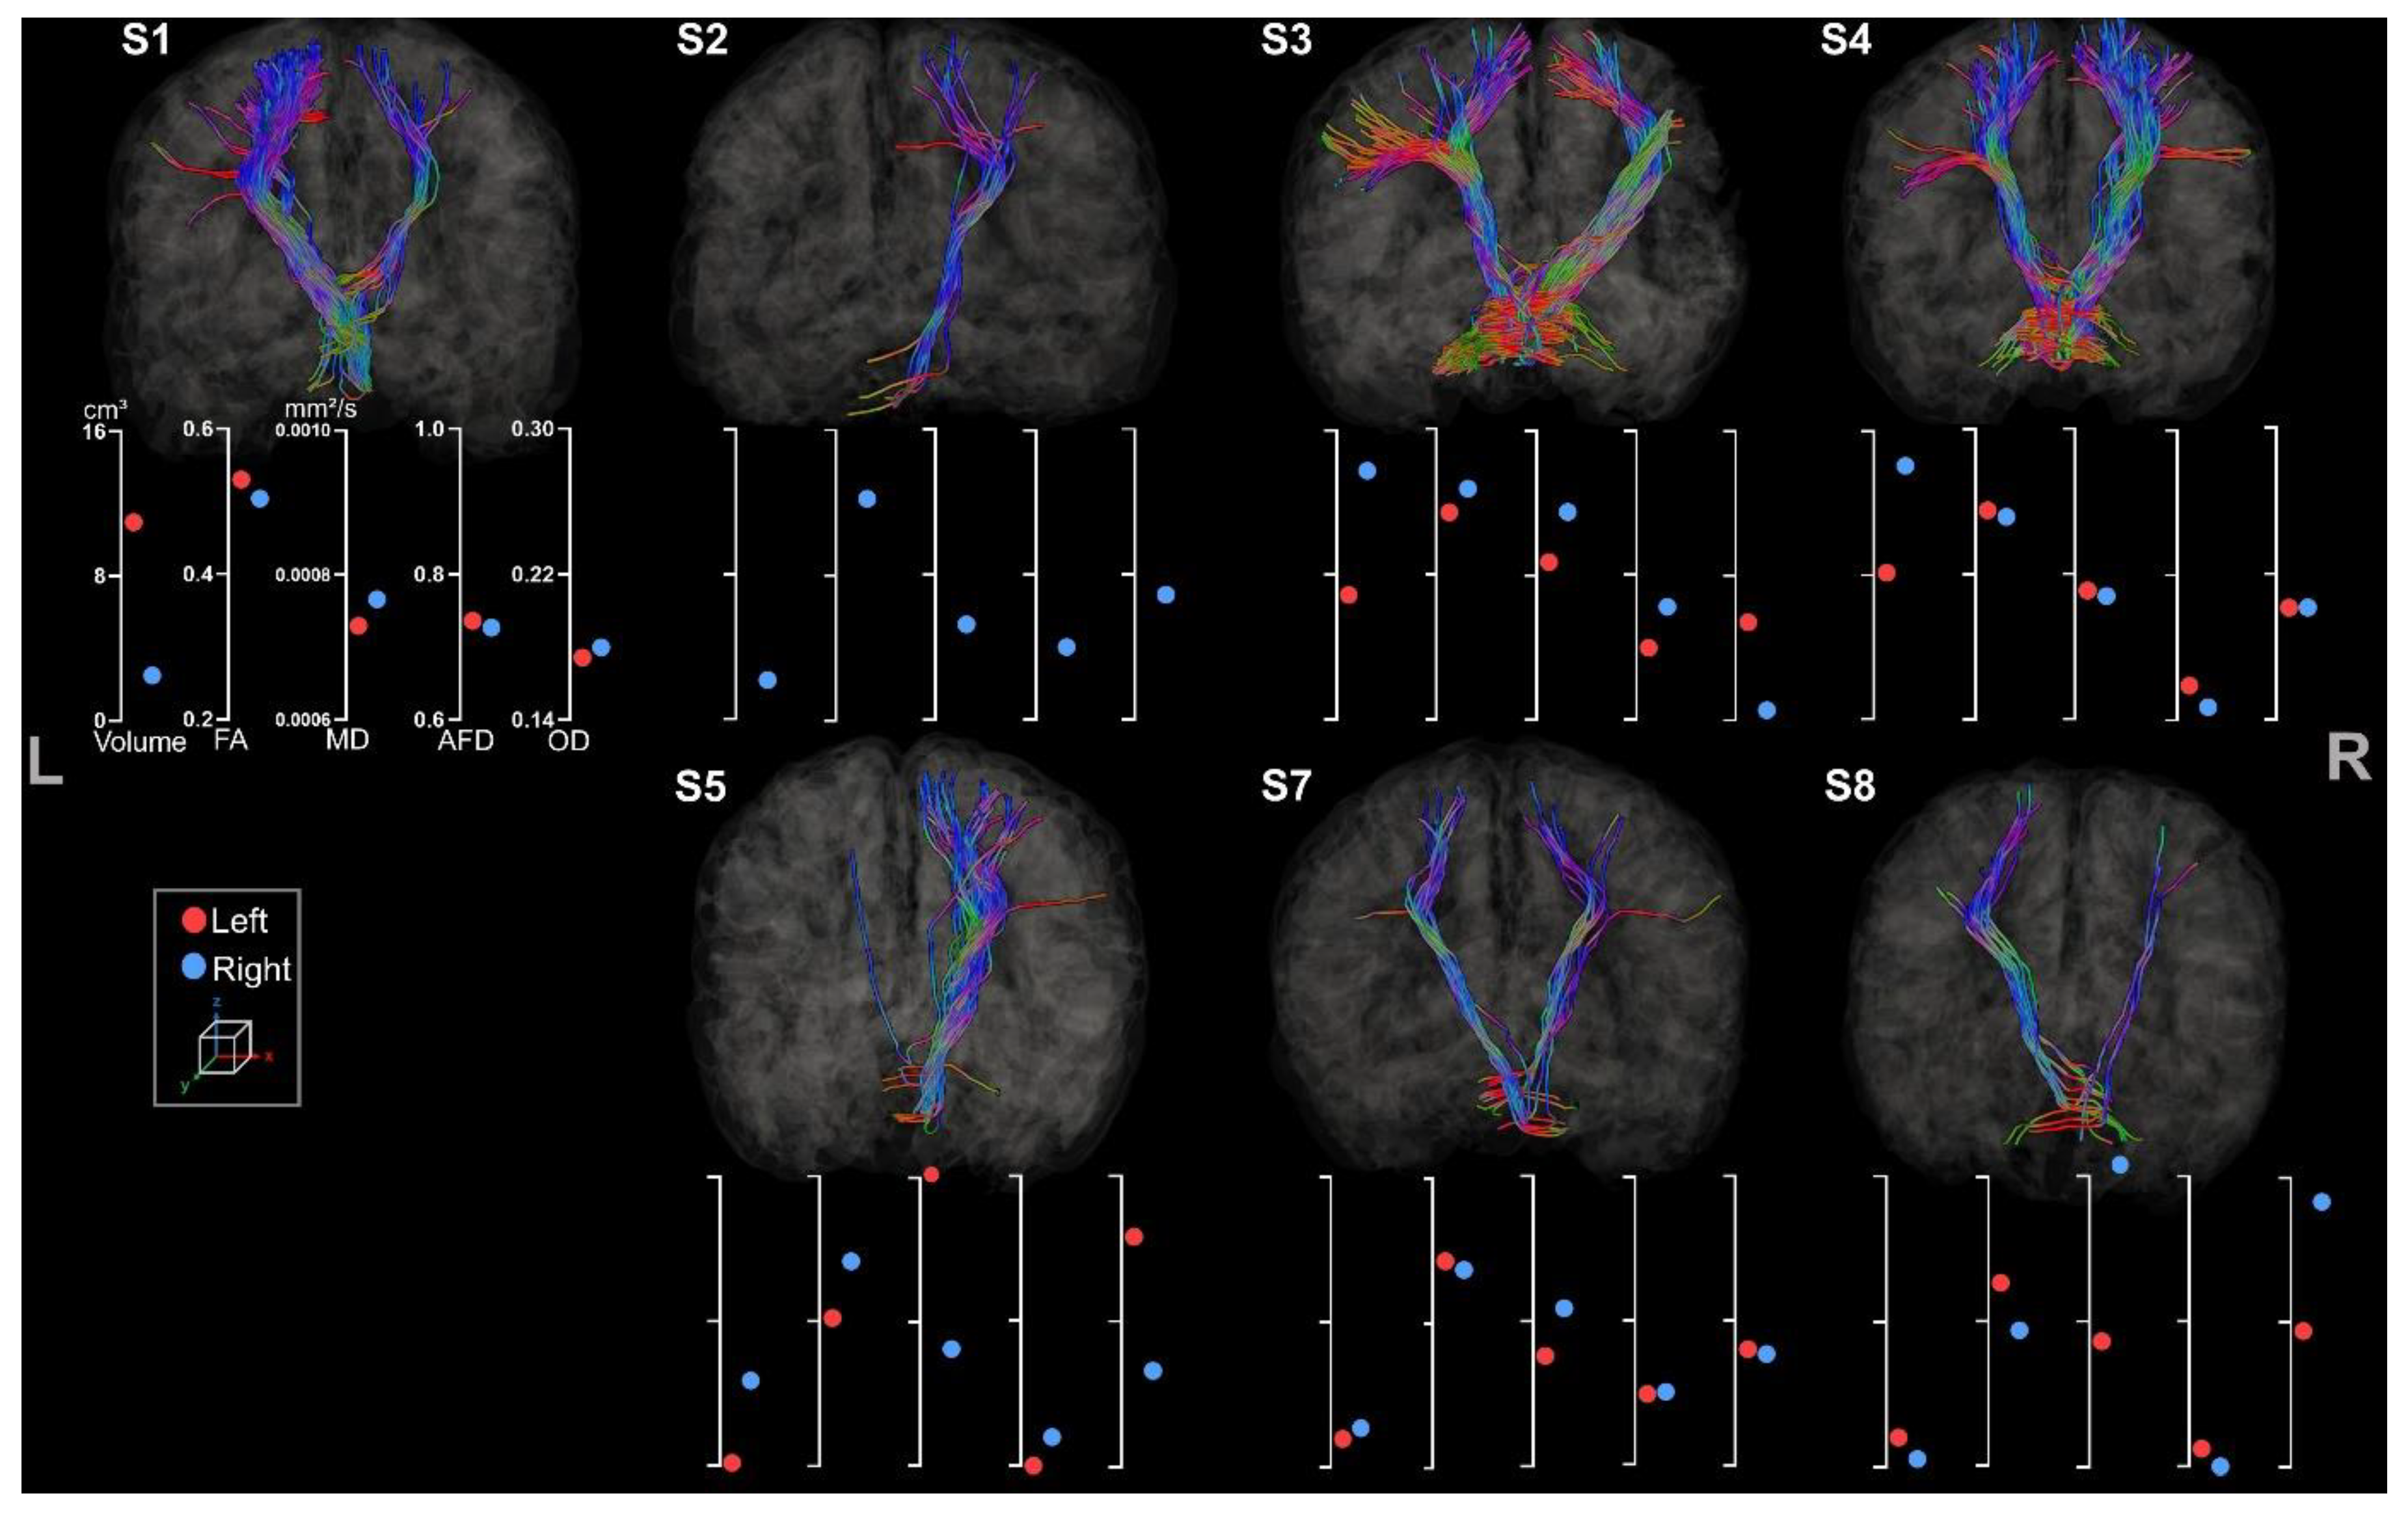

3.3.2. Fronto-Ponto-Cerebellar Tracts

3.3.3. Cerebello-Thalamo-Frontal Tracts